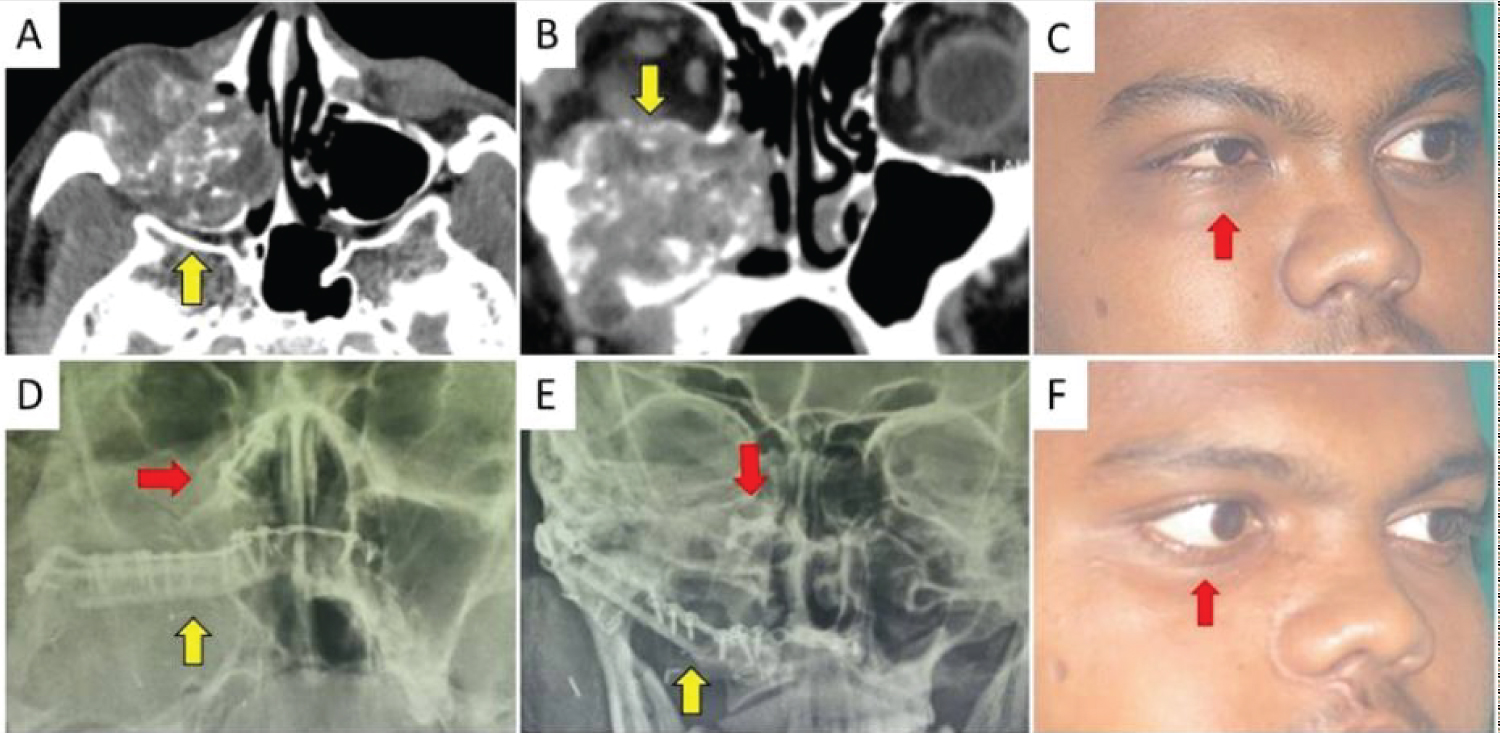

Post-surgical histopathology report of the maxillectomy specimen showed undifferentiated spindle cell tumor suggestive of monophasic synovial sarcoma with all borders free of tumor. Patient is on a regular follow up with good functional and esthetic outcome (Figure 3).

Figure 3: Preoperative and Postoperative comparison (A) Preoperative CT scan axial section showing expansion of posterior maxilla denoted by an arrow; (B) CT scan coronal section showing tumor spreading into intranasal compartment and floor of orbit (arrow); (C) Preoperative right oblique lateral photograph showing proptosis of right eye and right infraorbital swelling denoted by an arrow; (D) Post operative PNS view radiograph showing plate fixing coronoid process to medial nasal bone (horizontal arrow) and plates fixing fibula to right zygoma and left maxilla (vertical arrow); (E) PA view radiograph showing plate fixing coronoid process to medial nasal bone (inverted arrow) and plates fixing fibula to right zygoma and left maxilla (arrow); (F) Postoperative right oblique lateral photograph showing complete symmetry excepting mild ectropion of right eye denoted by an arrow. View Figure 3